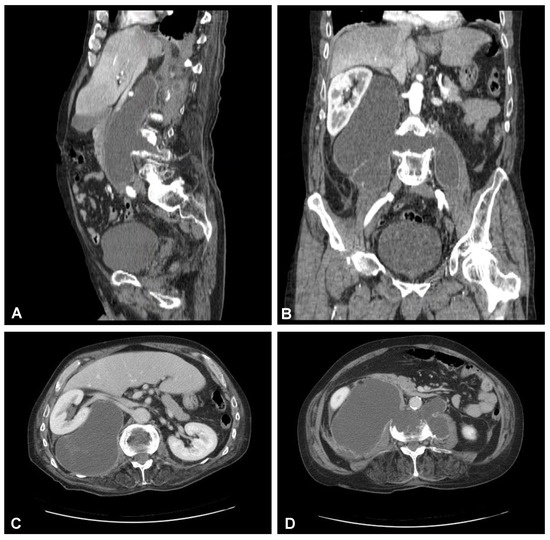

Figure 3. Preoperative sagittal (A), coronal (B), and axial (C,D) CT scans (contrast enhanced) of the lumbar spine demonstrating hypodense area with enhancing wall at the L3/L4 intervertebral disc space communicating with both psoas major muscles forming massive well-defined fluid-like collection in the right retroperitoneum.

A 59-year-old man presented to the hospital with atypical abdominal pain for a few days, three weeks after sustaining a low-energy fall. At the time of admission, the patient had normal upper and lower extremity strength and no pathologic reflexes, as well as no bowel or bladder incontinence. The initial performed plain radiograph of the abdomen demonstrated a fracture line completely slicing through the L3/L4 intervertebral disc space and features of ASH (Figure 1). The additional performed computed tomography (CT) scans demonstrated a three-column fracture of L4 vertebrae with a suspicious transdiscal injury at the L3/L4 level, which was morphologically classified as type B3/C according to the Arbeitsgemeinschaft für Osteosynthesefragen (AO) spine classification. Moreover, at the fracture level, the hypodense area communicating intervertebral disc space with both psoas major muscles forming a massive, well-defined fluid-like collection in the right retroperitoneum was observed (Figure 2). In addition, contrast-enhanced CT (CE-CT) showed a thick enhancing wall and internal septae within an area measuring a total of 10 cm × 20 cm × 10 cm (TR × AP × CC) (Figure 3). Furthermore, the performed magnetic resonance imaging (MRI) scans confirmed the cystic nature of the lesion, which had no specific characteristics and demonstrated intensities that were similar to those of cerebrospinal fluid (CSF) (Figure 4). Taking into consideration the history and radiological features, suspicion of spondylodiscitis with osteomyelitis features and retroperitoneal abscess formation was provided by the radiologist. Blood analysis performed on admission revealed the following results: hemoglobin (Hb): 9.6 g/dL; platelet (PLT): 192 × 109/L; white blood cell (WBC): 9.7 × 109/L; and creatinine (CREA): 0.42 mg/dL. Despite the lack of infection symptoms, the patient was empirically administered intravenous antibiotics, including meropenem (1 g every 8 h) and vanomycin (1 g every 12 h), without waiting for microbiological confirmation.